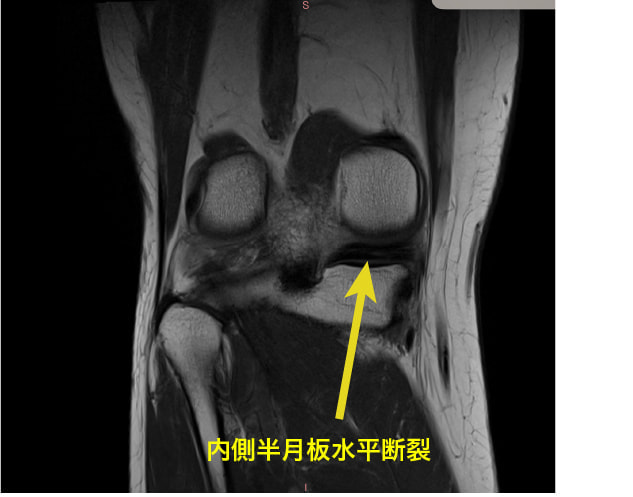

上記に紹介している膝のMRIは変形性膝関節症の原因の1つとして指摘されている、「内側半月板後根(後節)損傷MMPRT」の一症例です。

膝関節の方面のCOR画像(前額面)ですが、内側半月板の水平断裂が見られます。

症例:半月板の逸脱

半月板hoop機能(荷重ストレスの分散)の破綻が急激な変形性膝関節症の進行の一因とされています。

軸方向の機械的ストレスの約70%が半月板を介して分散されていることを考えれば、半月板の損傷や逸脱によって変形性膝関節症に発展することは想像ができるでしょう。

内側半月板の前角と後角は、関節包や靭帯と連続しつつ、骨へ強固に付着しています。この骨への付着部は、半月板が関節にかかる荷重を分散する際の固定点として機能し、適切な位置で半月板が荷重を受けることを可能にします。特に、内側半月板の後根部の付着は、関節の荷重負荷に対抗するための重要な要素です。

半膜様筋が関節包に付着し、その関節包の張力に関与しているため、内側半月板の逸脱に関してのターゲットは「膝関節のアライメント調整」と「半膜様筋の促通」です。